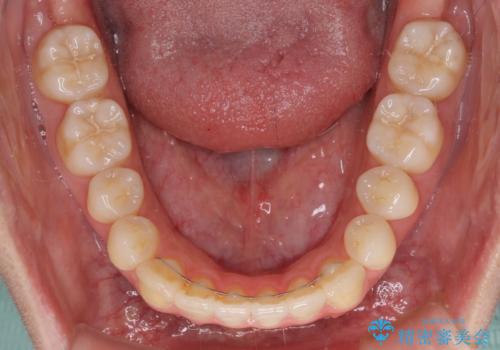

オープンバイトでかみにくい インビザラインによる矯正治療

- 前歯の上下スペースによる食べにくさを気にして来院された患者様です。

インビザラインにより上下の前歯の隙間を閉じていくこととしました。

上下の奥歯を圧下させるようにすることで、前歯を接触させるように計画しました。

上下の隙間に舌が入り込むことがオープンバイトの原因であったため、舌の筋肉のトレーニングも並行して行い、後戻りの抑制を図りました。